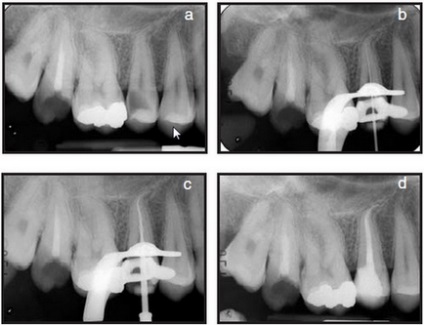

Klinikai eset №1.

a) A második felső állkapocs kisőrlő jobb jeleivel akut gyulladás a cellulóz.

b) meghatározása munkahossz egy acél fájlt. Megjegyezzük, hogy a gyökere a fog erősen ívelt, és van egy kis vastagságú dentin falak csúcsi kétharmadát.

c) Mtwo 20.06 eszköz be a munkahossz.

d) kitöltése a gyökércsatorna rendszer. Az eszköz Mtwo 40.04 használtunk master file. Mentése csatorna anatómia és szövet-megtakarító gyökér arányt értek el, még viszonylag nagy csúcsi kiterjesztése.

Klinikai eset №2.

a) A második felső állkapocs kisőrlő jobb jeleivel akut gyulladás a cellulóz.

b) Mtwo 20.06 eszköz be a munkahossz.

c, d) kitöltése a gyökércsatorna rendszer előkészítés után Mtwo eszközöket a standard szekvencia és Mtwo A1 (a különböző előrejelzések).

a) Az első felső állkapocs kisőrlő a jelzések endodonciai kezelés. Meghatározása munkahossz egy acél fájlt.

b) kitöltése a gyökércsatorna rendszer előkészítés után csatorna Mtwo eszközöket a standard szekvencia és Mtwo A1.